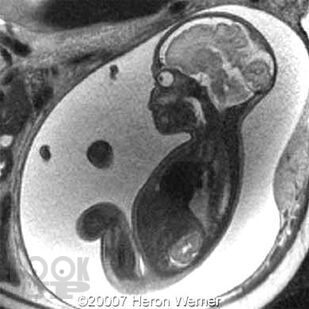

Врождённые аномалии желудочно-кишечного тракта у детей

Учебное пособие полностью соответствуют требованиям ФГОС ВО (2020). Данное учебное пособие посвящено вопросам клиники, ранней диагностики и лечения врождённых аномалии желудочно-кишечного тракта у детей. Учебный материал адаптирован к образовательным технологиям с учетом специфики обучения на педиатрическом и лечебном факультете. Пособие иллюстрировано рисунками и рентгенограммами, имеются ситуационные задачи и тестовые задания.